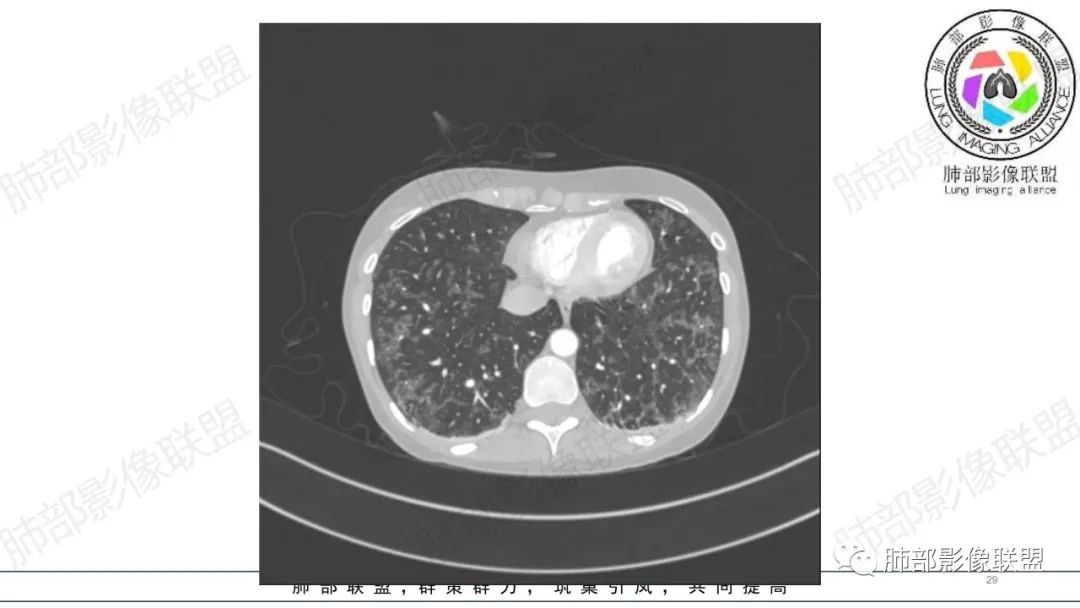

34岁女性患者,“哮喘”病史30年,近期有可疑刺激性气体吸入史;因乏力半年,咳嗽、憋气、发热4天就诊;6.1CT提示双肺广泛毛玻璃影及粟粒样结节,胸膜下闲置及血管周闲置,可见树丫征,部分小叶间隔增厚。考虑:1.过敏性肺泡炎,有可疑刺激气体接触史,胸膜下闲置,广泛毛玻璃影,地图样分布,粟粒结节边界模糊,支持过敏性肺泡炎,但糖皮激素治疗效果不佳,且动态复查血常规血红蛋白进行性降低,过敏性肺泡炎 不符合;2.肺含铁血黄素沉积症:患者30“哮喘”病史,可能为肺含铁症状,肺部CT提示双肺弥漫毛玻璃影及粟粒结节影,中下肺明显,肺底部分小叶间隔增厚,近期咳嗽、憋气、发热,血常规血红蛋白进行性下降,考虑肺含铁急性期症状,但临床无咯血症状,肺含铁不典型。综合考虑:肺含铁血黄素沉积症>过敏性肺泡炎。

年轻女性 ,急性喘息发热,肺部影像弥漫磨玻璃密度,部分细小腺泡结节,胸膜下黑线显示,短期复查,病变密度增高,下肺明显,血管周围肺组织累及较少、且逐渐成小叶间隔分布。考虑弥漫肺泡内病变,并经淋巴道转移,下肺比上肺明显,多为免疫细胞功能下肺较强。1.过敏性肺泡炎,有相关病史,三层密度特点、头尾测分布,符合。2 肺泡微石症,多有钙化,且缓慢起病,病程不太符合,放待排。3 吸入相关肺损伤,有病史,疾病演变过程也符合渗出-肉芽肿改变,建议详细询问病史。4 感染性病变,结核?病变气道分布为主,如此弥漫且没有树丫不符合。5.巨细胞病毒,可以磨玻璃 结节 改变,没有免疫缺陷病史。最后考虑吸入所致 1过敏性肺泡炎、吸入性肺损伤 鉴别肺泡微石症。

肺内气腔磨玻璃结节,肝脾肿大,治疗后间质改变,弥漫大B可能